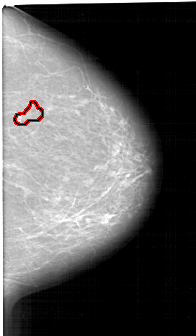

FILE: A_1349_1.RIGHT_CC.OVERLAY

TOTAL_ABNORMALITIES 1

ABNORMALITY 1

LESION_TYPE CALCIFICATION TYPE PLEOMORPHIC DISTRIBUTION SEGMENTAL

ASSESSMENT 4

SUBTLETY 4

PATHOLOGY BENIGN

TOTAL_OUTLINES 1

BOUNDARY